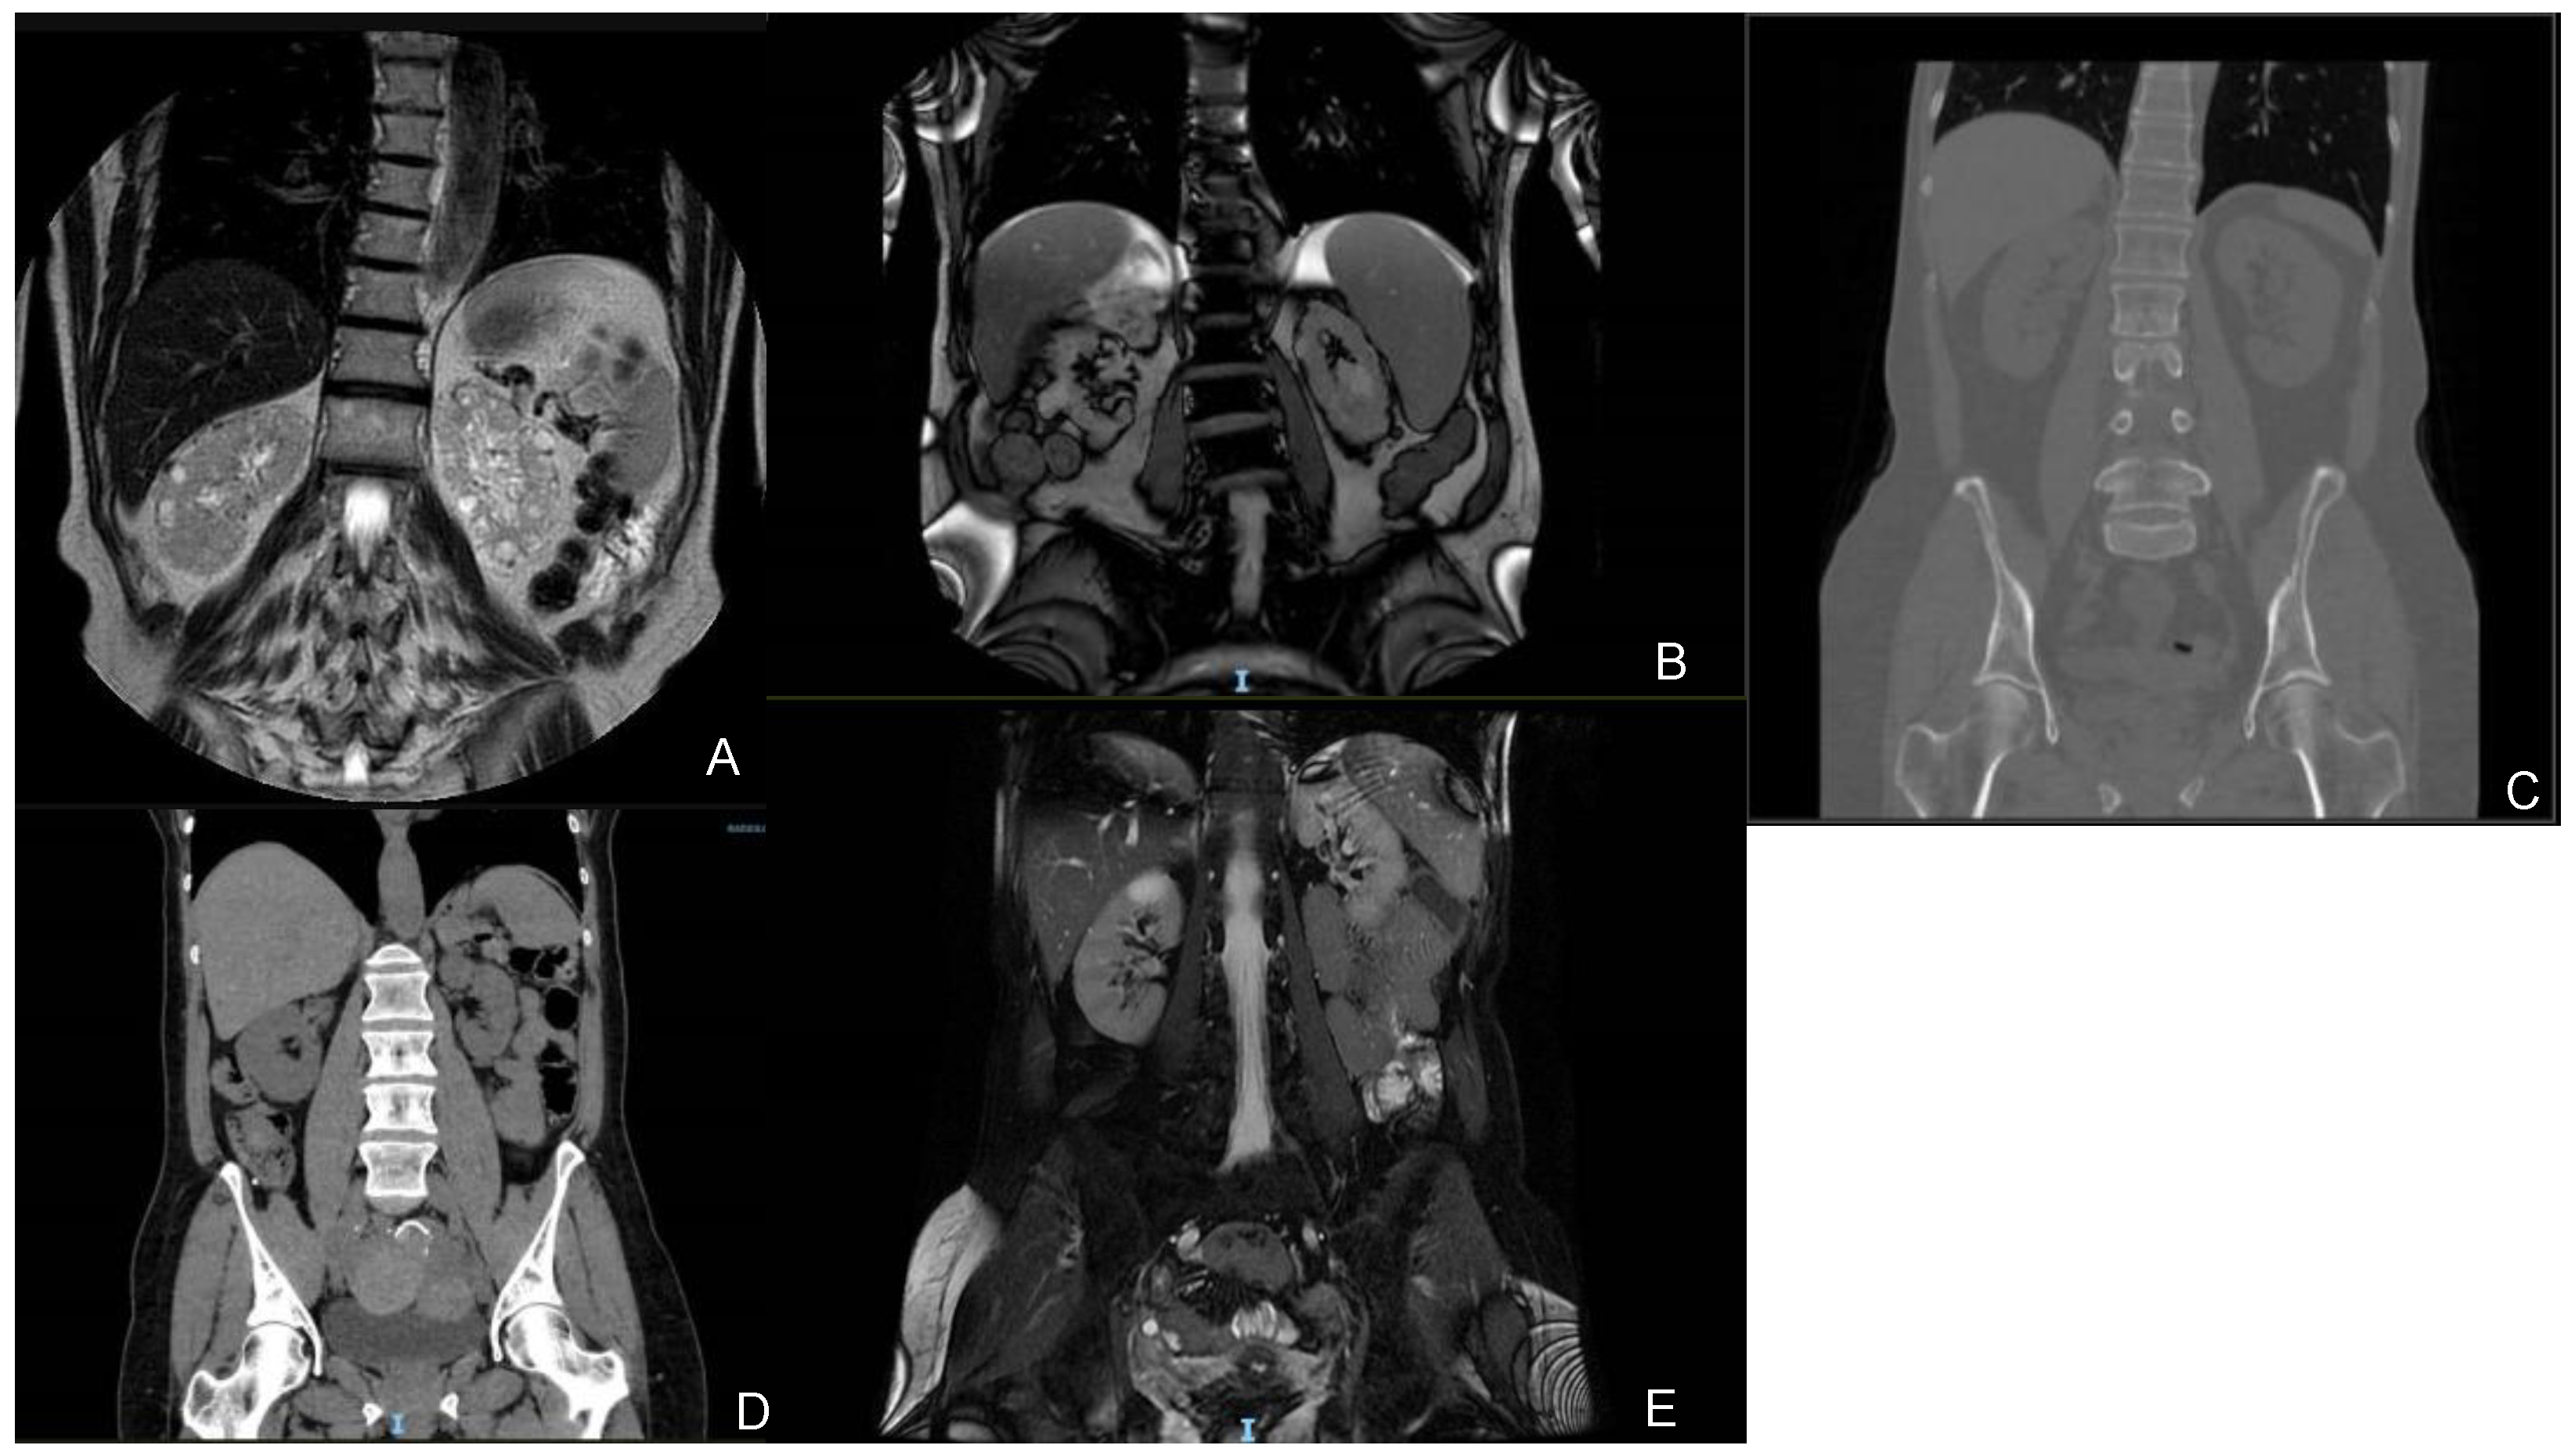

| Patient 1 (67) | NM_016306.5:c.716T>G p.(Leu239Ter) 4 / | Regular-sized kidneys (10/10) Bilateral cortical millimetric cysts | No cysts | Yes (67) | Creat. 1.58 mg/dL eGFR 46 mL/min/1.73 m2 CKD IIIa | Creat. 2.50 mg/dL eGFR 26 mL/min/1.73 m2 CKD IV | −4 | MGUS, mild bilateral perceptive hearing loss, hyperuricemia |

| Patient 2 (67) | NM_016306.5:c.134A>G p.(Tyr45Cys) 4 gnomAD Exomes: Version: 2.1.1ƒ = 0.00000797; gnomAD GenomesVersion: 2.1.1ƒ = 0.0000319 | Regular-sized kidneys (11/13) Bilateral millimetric cysts and some bigger cysts | No cysts | Yes | Creat. 2.45 mg/dL eGFR 27 mL/min/1.73 m2 CKD IV | Creat. 4.16 mg/dL eGFR 14 mL/min/1.73 m2 CKD V | −4.3 | Nephrolithiasis, AMI, AF, severe mitral insufficiency |

| Patient 3 (61) | NM_016306.5:c.456+3_456+6del (IVS4) 4 / | Regular-sized kidneys (10.9/10.5) Bilateral millimetric cysts | No cysts | Yes (55) | Creat. 1.04 mg/dL eGFR 59 mL/min/1.73 m2 CKD IIIa | Creat. 1.14 mg/dL eGFR 52 mL/min/1.73 m2 CKD IIIa | −2.3 | Microhaematuria, recurrent cystitis, nephrolithiasis, mild tricuspid insufficiency, mild neurosensorial hearing loss in the left ear |

| Patient 4 (59) | NM_016306.5:c.456+3_456+6del (IVS4) 4 / | Regular-sized kidneys (10.3/9.4) Bilateral millimetric cysts | Multiple cysts | Yes (50) | Creat. 1.27 mg/dL eGFR 46 mL/min/1.73 m2 CKD IIIa | Creat. 1.27 mg/dL eGFR 46 mL/min/1.73 m2 CKD IIIa | N/A | / |

| Patient 5 (46) | NM_016306.5:c.499C>T p.(Arg167Trp) 3 gnomAD ExomesVersion: 2.1.1ƒ = 0.00000398; gnomAD GenomesVersion: 2.1.1 / | Regular-sized kidneys (10/10) Bilateral millimetric cysts | One cyst in the III segment (4 mm) | No | Creat. 1.54 mg/dL eGFR 40 mL/min/1.73 m2 CKD IIIa | Creat. 1.54 mg/dL eGFR 40 mL/min/1.73 m2 CKD IIIa | N/A | Hyperuricemia, reactive anxiety depressive syndrome |